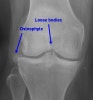

영상 검사

X-ray에서는 보이지 않을 수 있으므로 주의해야 합니다(*radioopaque body의 경우에만 찾을 수 있습니다).

- radioopaque body(대부분의 경우)

a. 골연골 파편(osteochondral fragment) : 박리성 골연골염(OCD), 골연골 골절(osteochondral fracture), OA, synovial chondromatosis 등